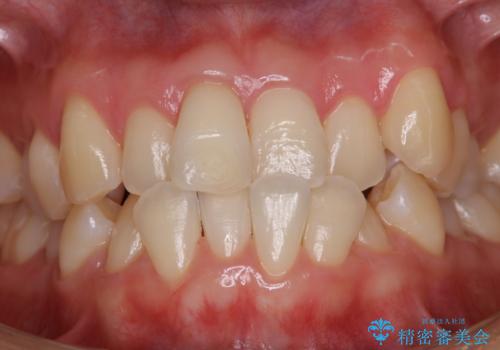

- 矯正治療がまもなくスタートするため、きれいにしたいのと歯磨きを上達したいとのことでした。染め出しをしての歯磨きチェック・指導とPMTC30分コースを行いました。